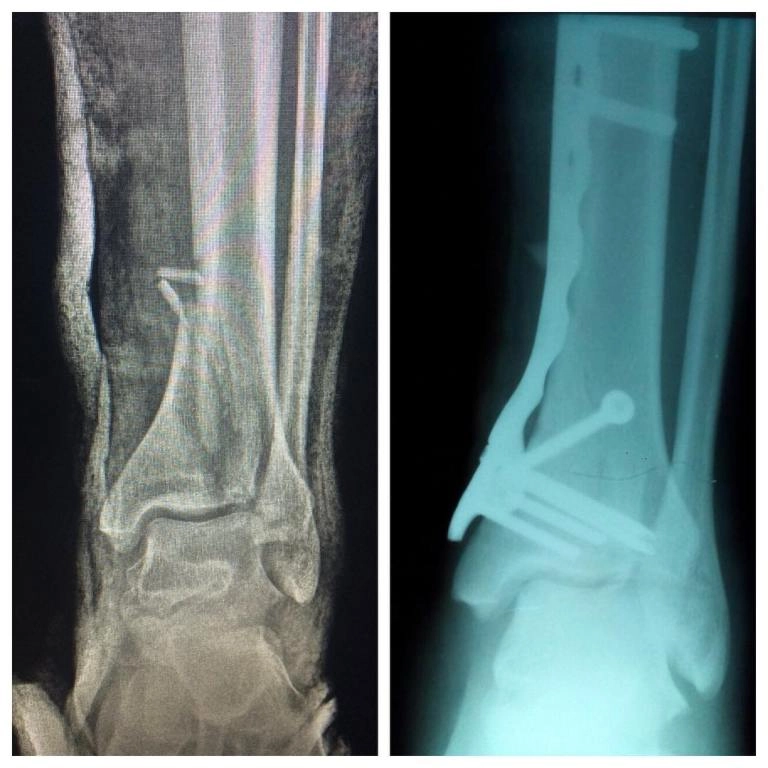

• Также востребованы процедуры по восстановлению связок, остеосинтез костей при переломах разной сложности.